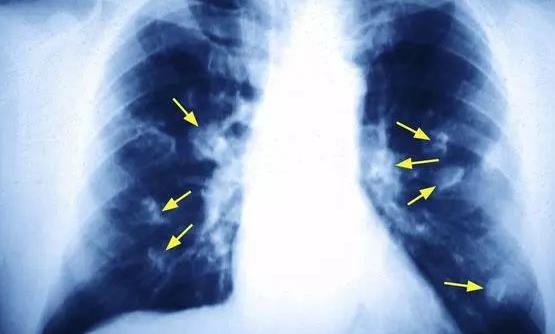

揪出引发女性肺癌的罪魁祸首 厨房油烟的危害超乎想象

我国国家癌症中心的最新报告显示,肺癌是女性第二高发的癌症,仅次于乳腺癌。40-50岁女性中肺癌患者人数已经接近男性,达到了1:1的比例。但是国内女性的吸烟率很低,为何发生肺癌的概率却如此...